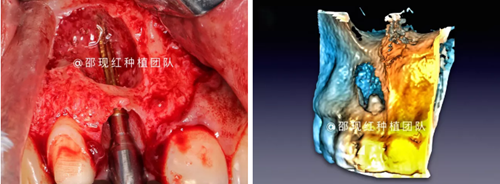

CASE ONE

11 12雙根尖聯(lián)合囊腫病例

術(shù)中使用科盧森骨粉